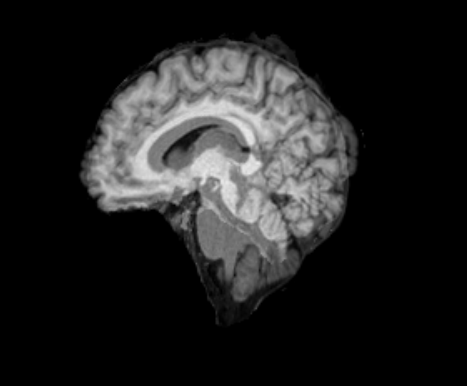

3.2.2 Robustness

In this experiment, we evaluate the robustness of Polaffini and the competing methods by computing a failure rate. We considered as potential outliers all cases for which the average Dice score over all regions after registration was below 0.34 (Z-score below -1.5, pooling Dices from all affine methods). All potential outliers were visually inspected to assess the reason behind the poor anatomical structure overlap score. All of them were clear failure cases, not just a residual misalignment to be expected after an affine registration. The failure counts for each method are reported in table 2. Almost all of the failure cases only occurred when registering with Flirt, mostly when subjects from the IXI dataset were involved. The most common failure type, showcased in Fig 6-a., consists of a local minimum where the frontal part of the moving brain is matched with the cerebellum of the reference one, a less frequent upside-down outcome is showcased in Fig 6-b. We suspect it is due to the fact that images from IXI have their axes ordered differently compared to the other two datasets and the template. However, since this information is contained in the header, it is unclear why Flirt could not handle the situation properly. Without the restriction of the angle search to , Flirt would give worse results (19 failure cases for subject-to-template and 61 for subject-to-subject). The only failure case using Anima for subject-to-subject is shown in Fig 6-c. For the rest of this section, we discard registrations if at least one of the methods has failed.

| reference | moving | moved | reference and moved | |

| a. | ukb_1154012-20252 | adni_AD-012-S-0720 | registered with Flirt | |

![]() |

|

| b. | ixi_165-HH-1589 | ukb_1145033-20252 | registered with Flirt | |

| c. | ixi_143-Guys-0785 | adni_MCI-003-S-6258 | registered with Anima-aff | |